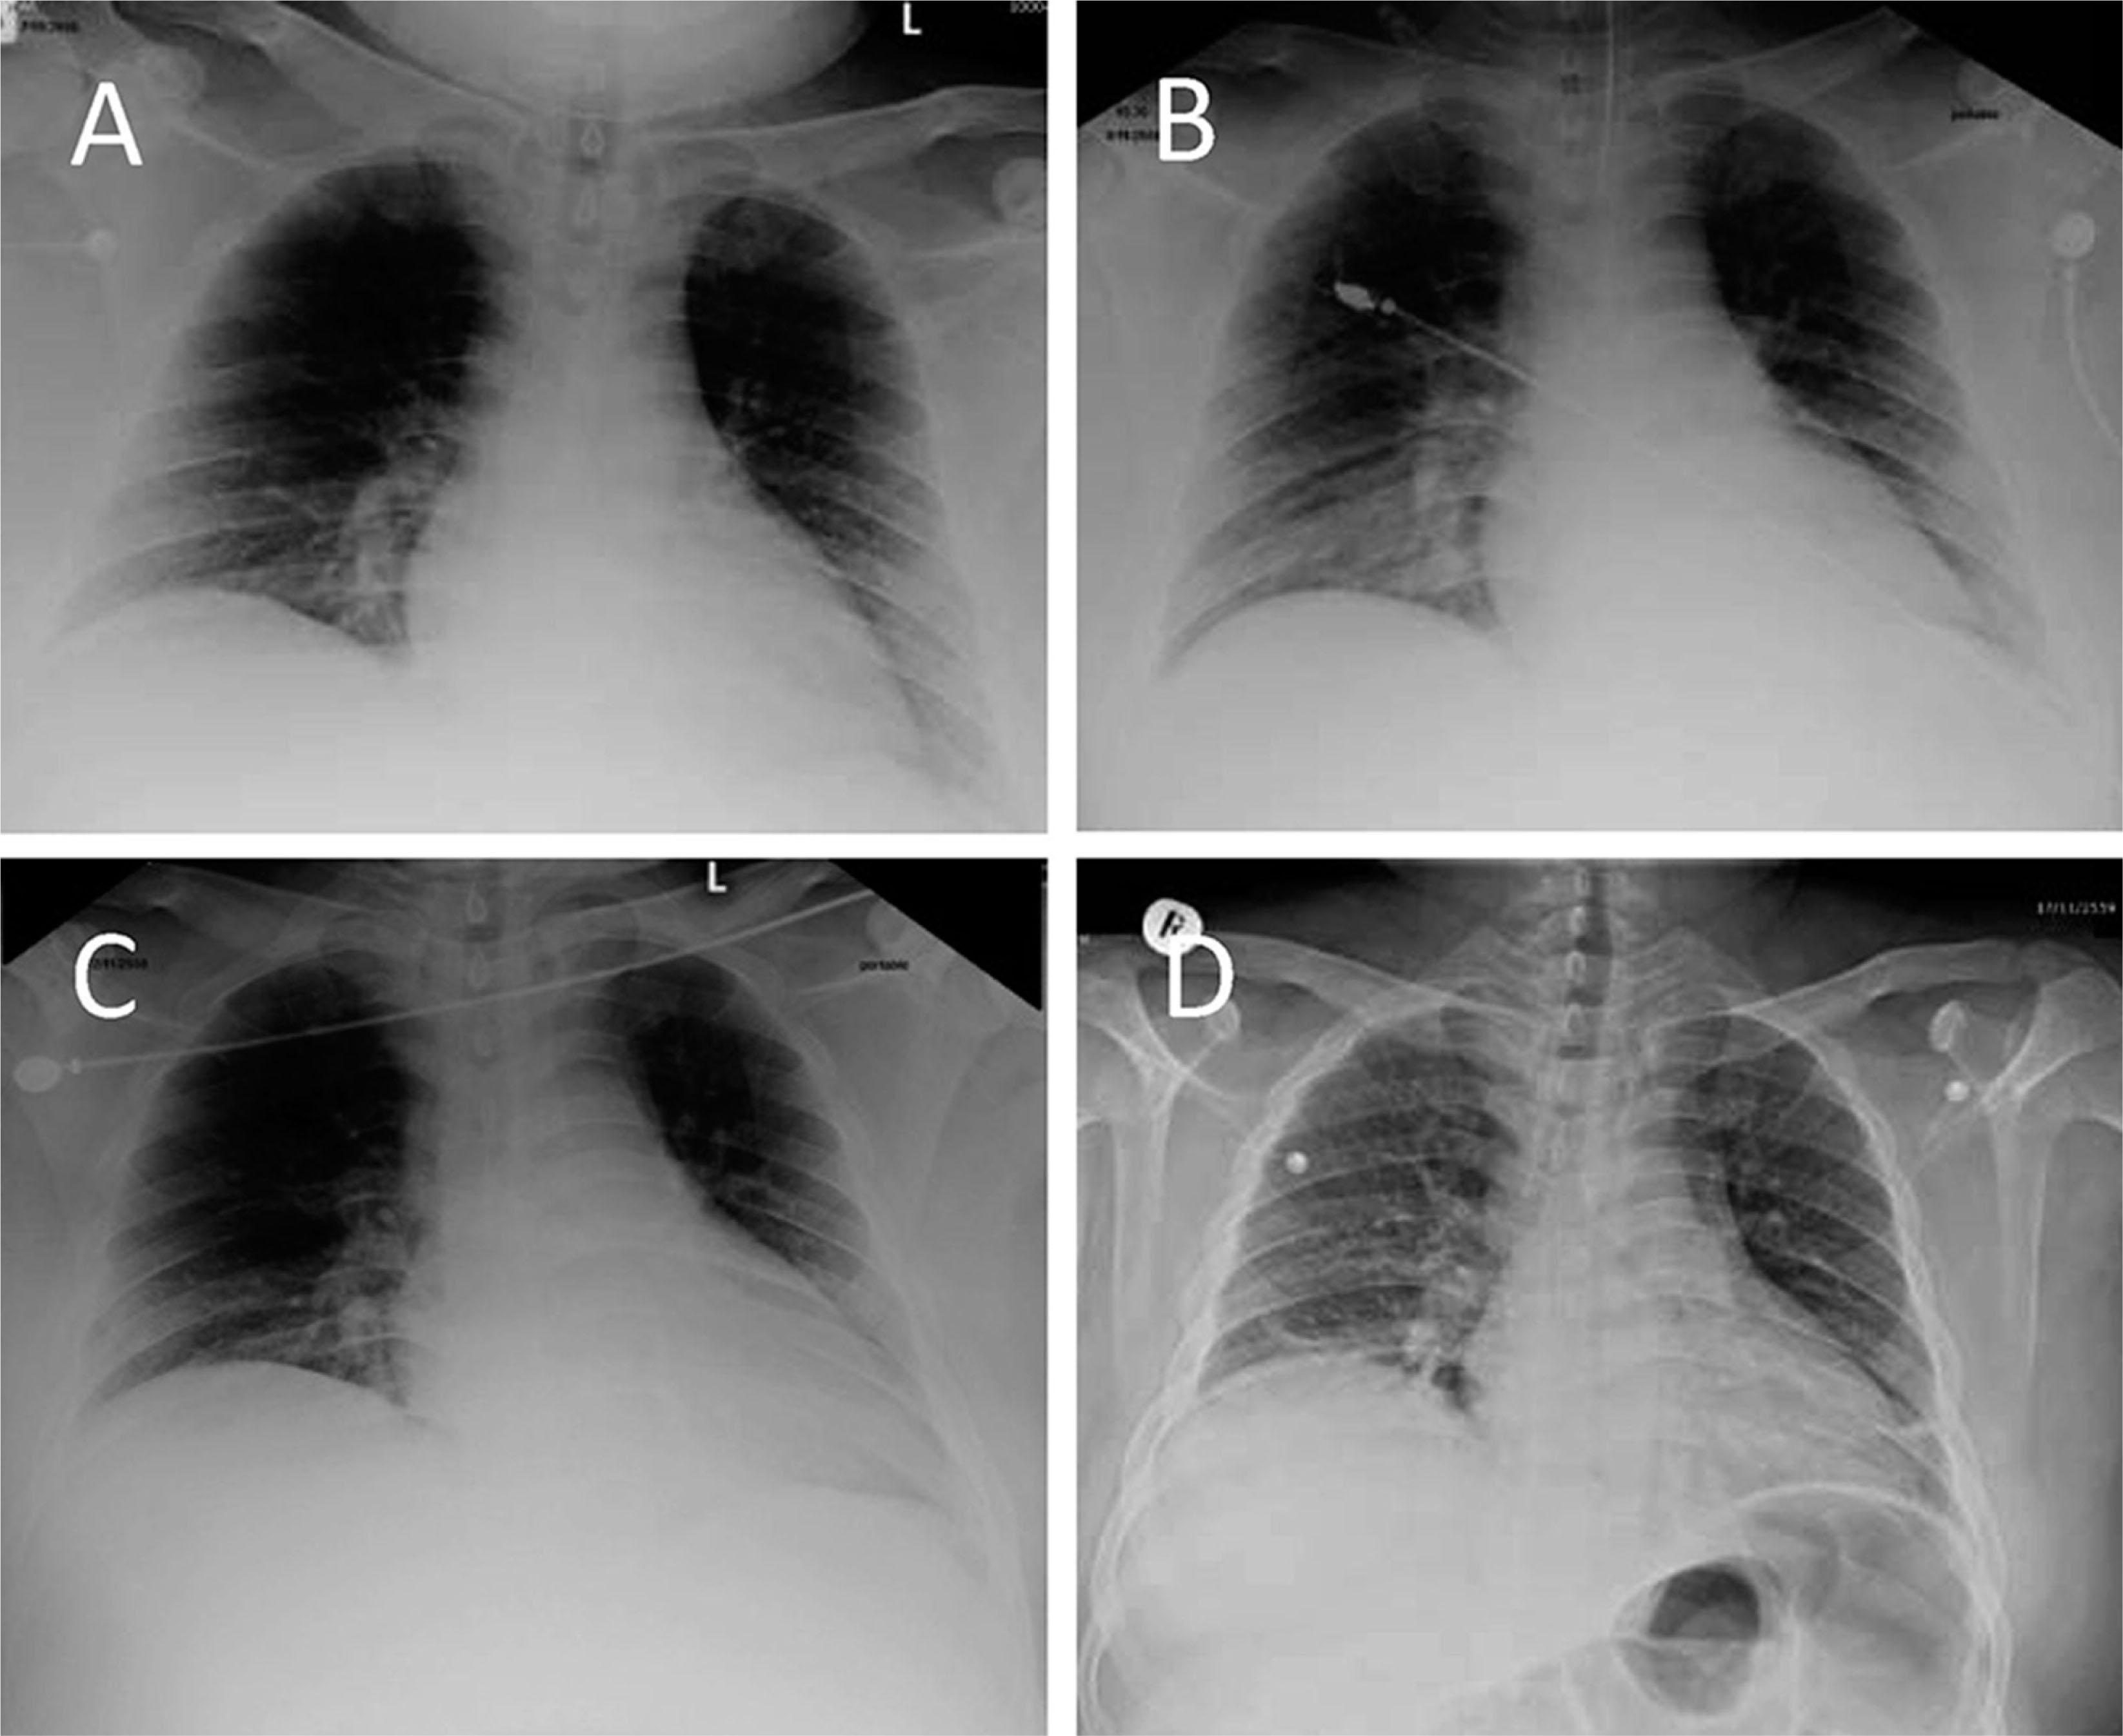

A. Posterior–anterior chest X-ray image demonstrating a slight radiographic sign that suggests interstitial pulmonary edema. B. Supine radiogram demonstrating redistribution of lung circulation from base to middle, suggestive of pulmonary congestion. C. Endotracheal tube inserted after persistent pulmonary congestion. D. Posterior–anterior chest X-ray image showing with normal lung marking and heart size.